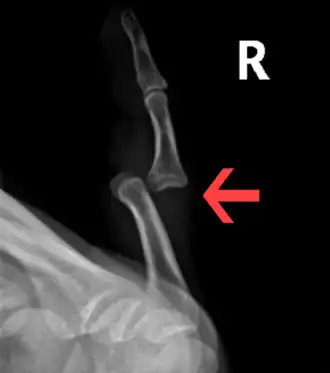

Radiograph of right fifth finger dislocation

Imaging Types

X-ray, usually a minimum of 2-views

• Generally, pre- and post-reduction X-rays are taken. Initial X-ray can confirm the dislocation and evaluate for any fractures. Post-reduction x-rays confirm successful joint alignment and can identify any injuries that may have been caused during the reduction procedure.[17]